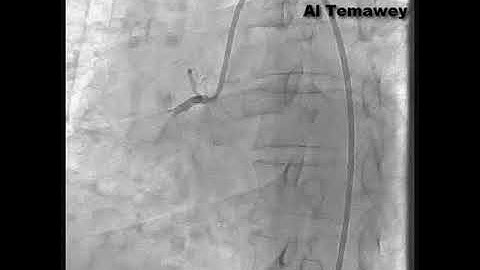

Case 177: Manual of CTO PCI - "A little too soon..."